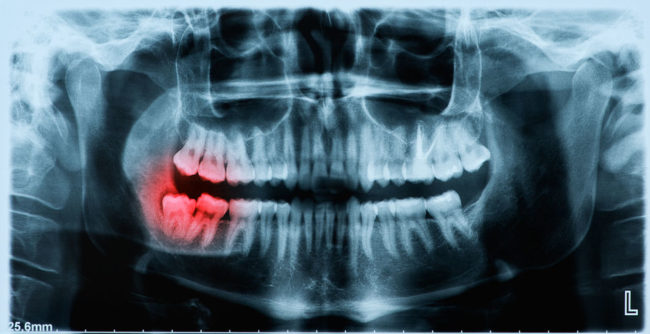

When someone sees you, your smile is the first thing that they notice. Smiling can demonstrate a person’s happiness, confidence, attractiveness, sociability, and sincerity. However, the effects of gum disease or other oral tissue disorders can not only be dangerous to your health and well-being, but also have the potential to ruin your smile. Luckily, periodontists (peri=around, dont=teeth)…